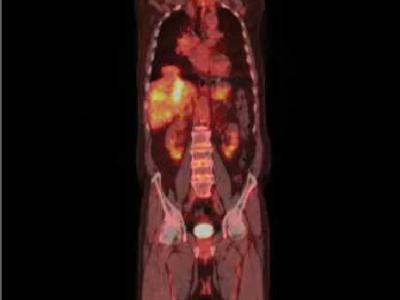

GCA patients with AORTITIS proven by CTA or FDG-PET/CT have higher rates of relapse. Among 82 GCA pts, 78% positive on both CTA & PET. Relapse was seen in 70% in the CTA+/PET+ group & 29% in the CTA-/PET+ (p = 0.019). https://t.co/psA6hywouL https://t.co/WORiBd9Qli